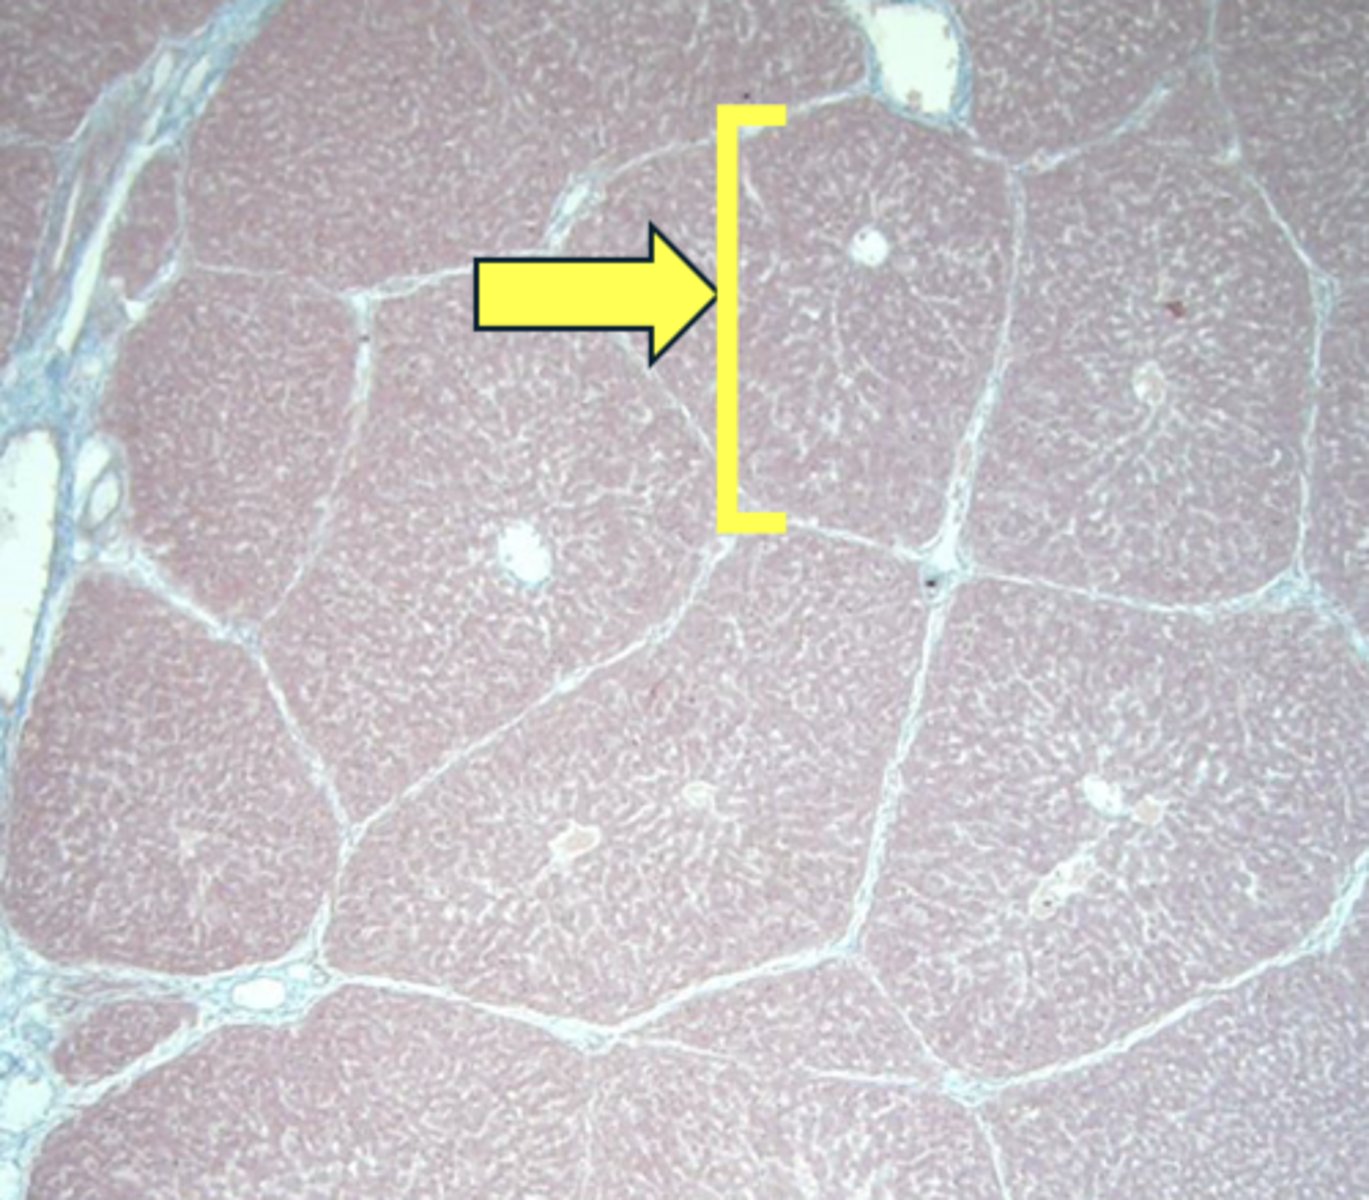

liver

name the tissue

lobule

(liver)

central vein

sinusoids

hepatocytes

type of cell

portal triad

(she said she won't show this on the microscope)